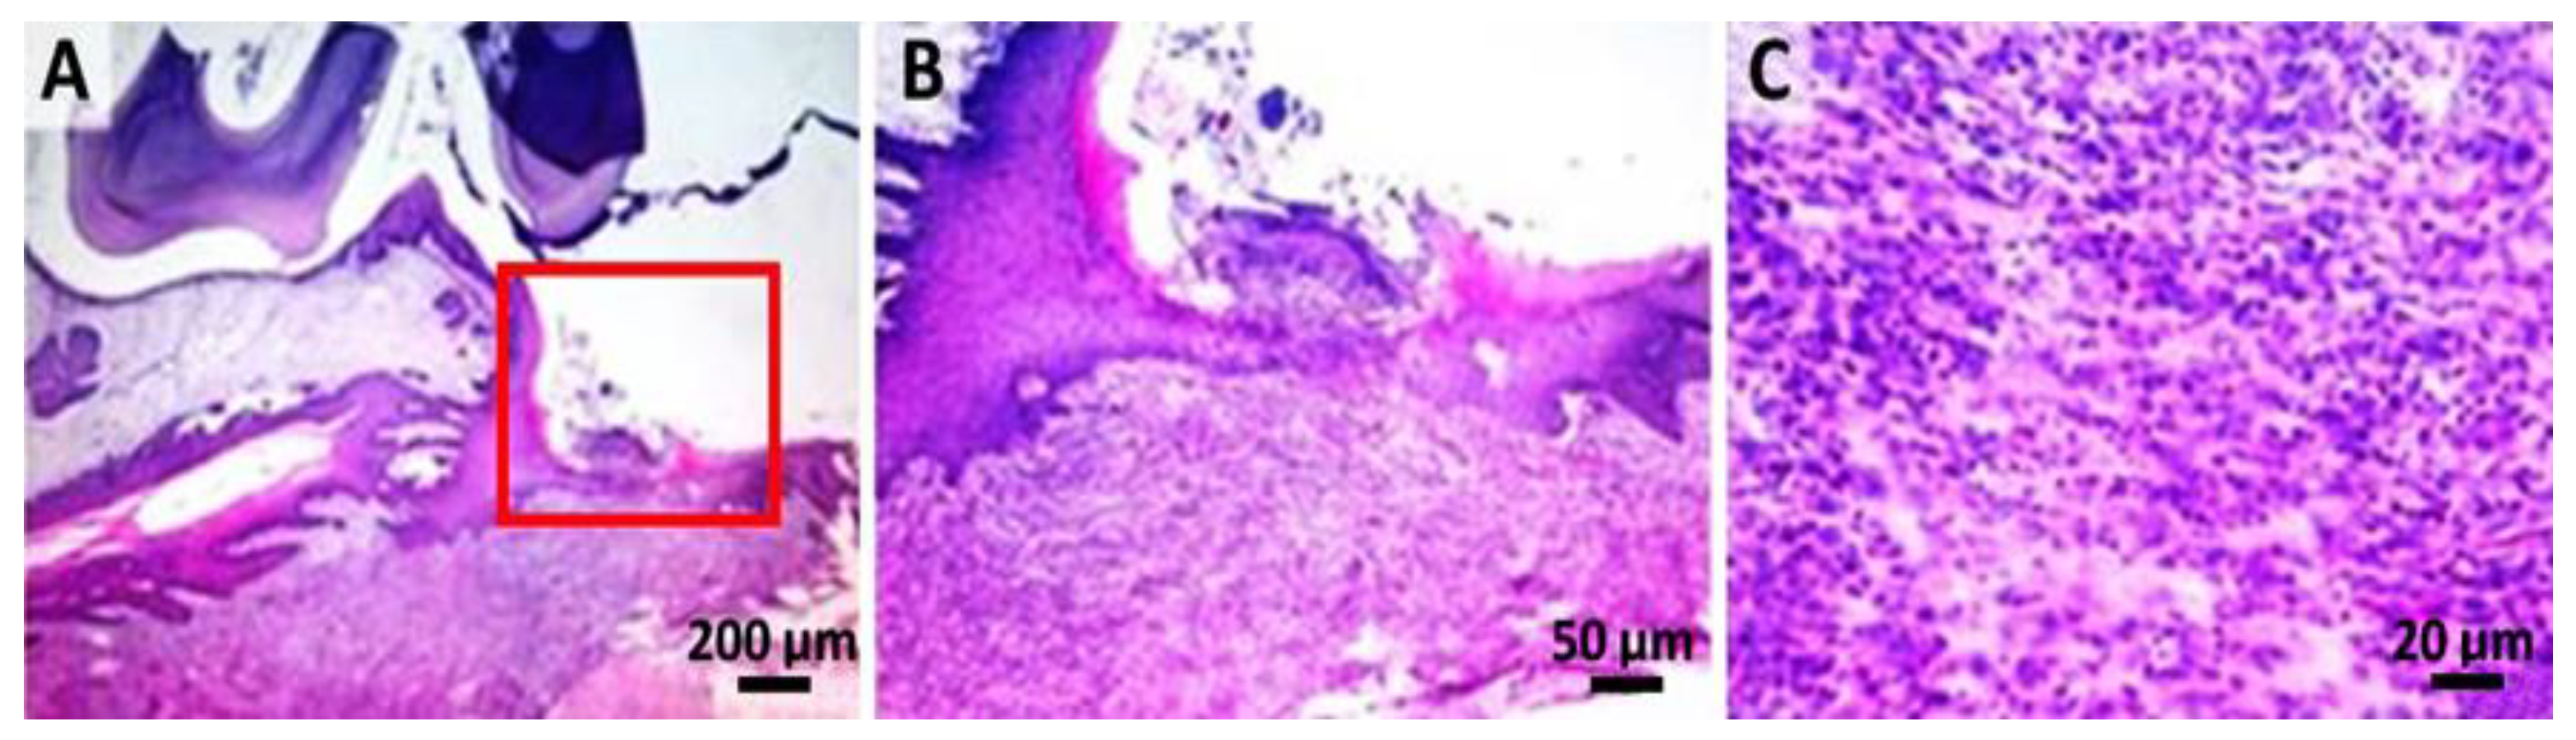

2.4. Histological Analysis

4.6. Histological Analysis